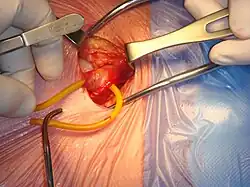

Open hernia repair

All techniques involve an approximate 10-cm incision in the groin. Once exposed, the hernia sac is returned to the abdominal cavity or excised and the abdominal wall is very often reinforced with mesh.[11] There are many techniques that do not utilize mesh and have their own situations where they are preferable.[25][17]

Open repairs are classified via whether prosthetic mesh is utilized or whether the patient's own tissue is used to repair the weakness. Prosthetic repairs enable surgeons to repair a hernia without causing undue tension in the surrounding tissues while reinforcing the abdominal wall. Repairs with undue tension have been shown to increase the likelihood that the hernia will recur. Repairs not using prosthetic mesh are preferable options in patients with an above-average risk of infection such as cases where the bowel has become strangulated (blood supply lost due to constriction).[21]